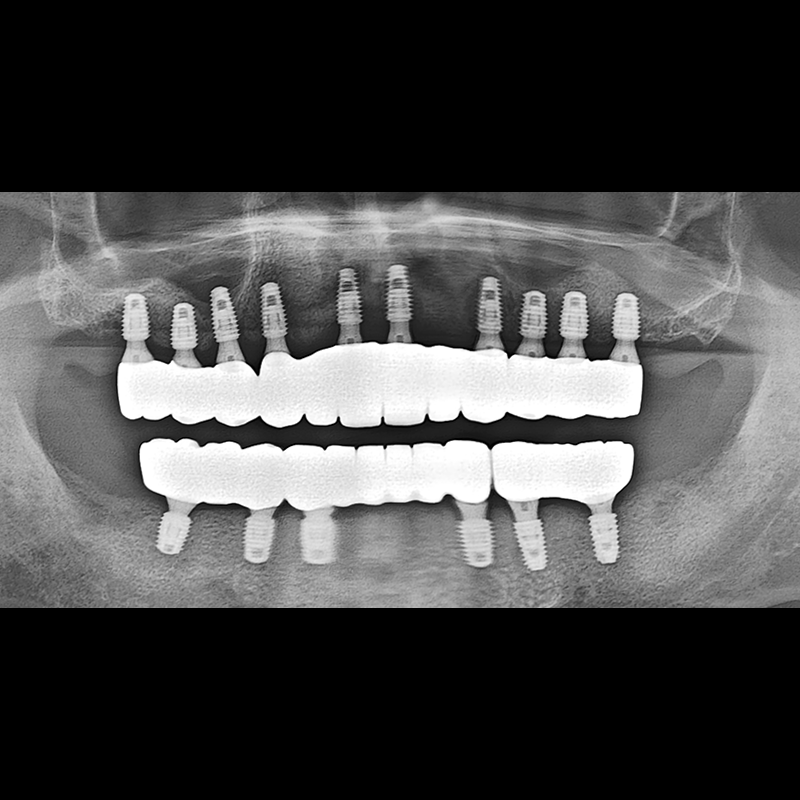

BEFORE AFTER

임플란트 전후사진 2025.05.30

결손된 치아 부분과 살리기 힘든 치아 위치에 임플란트를 식립하였습니다.